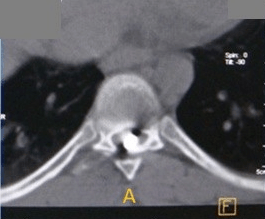

Un scanner avec reconstruction des coupes et une visualisation 3D a été réalisé, ne mettant en évidence aucune lésion osseuse, la balle semble s’être arrêtée au sein du nucleus pulposus (qui est le centre mou du disque intervertébral) au niveau de la colonne thoracique (niveau de Th8).

Ce qui est assez exceptionnel dans ce cas, c’est que le projectile n’ait pas créé de dégâts osseux au passage ce qui aggrave toujours les lésions médullaires mais en crée également par éclatement sur des structures alentour (notamment vasculaires).